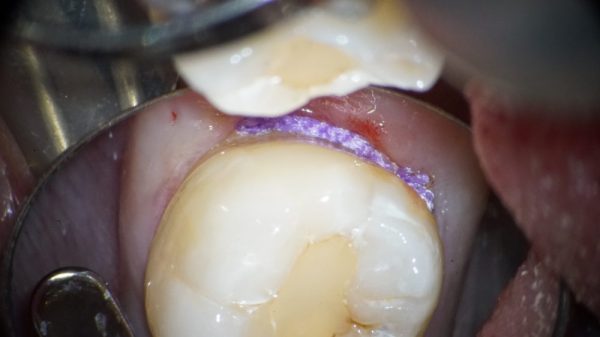

これは先ほどのレントゲンの方の口腔内写真です、

明らかに虫歯になっており、さらに汚れが溜まっているのがわかります。放置すればどんどん虫歯が進行してしまうでしょう。

虫歯とヒビが入っていたのでそこを削っていきます。

虫歯染め出し液を使用して、虫歯の範囲を明確にします。

虫歯を染めすことにより、虫歯の取り残しの防止と、健康な歯質を明確にするので、削る量を最小限にして、かつ虫歯をしっかり取り除くことができます。

(圧排糸)歯と歯茎の境目を明示したり、出血や浸出液のコントロールのために、青い糸を歯と歯茎の境目においています。治療後に外します。